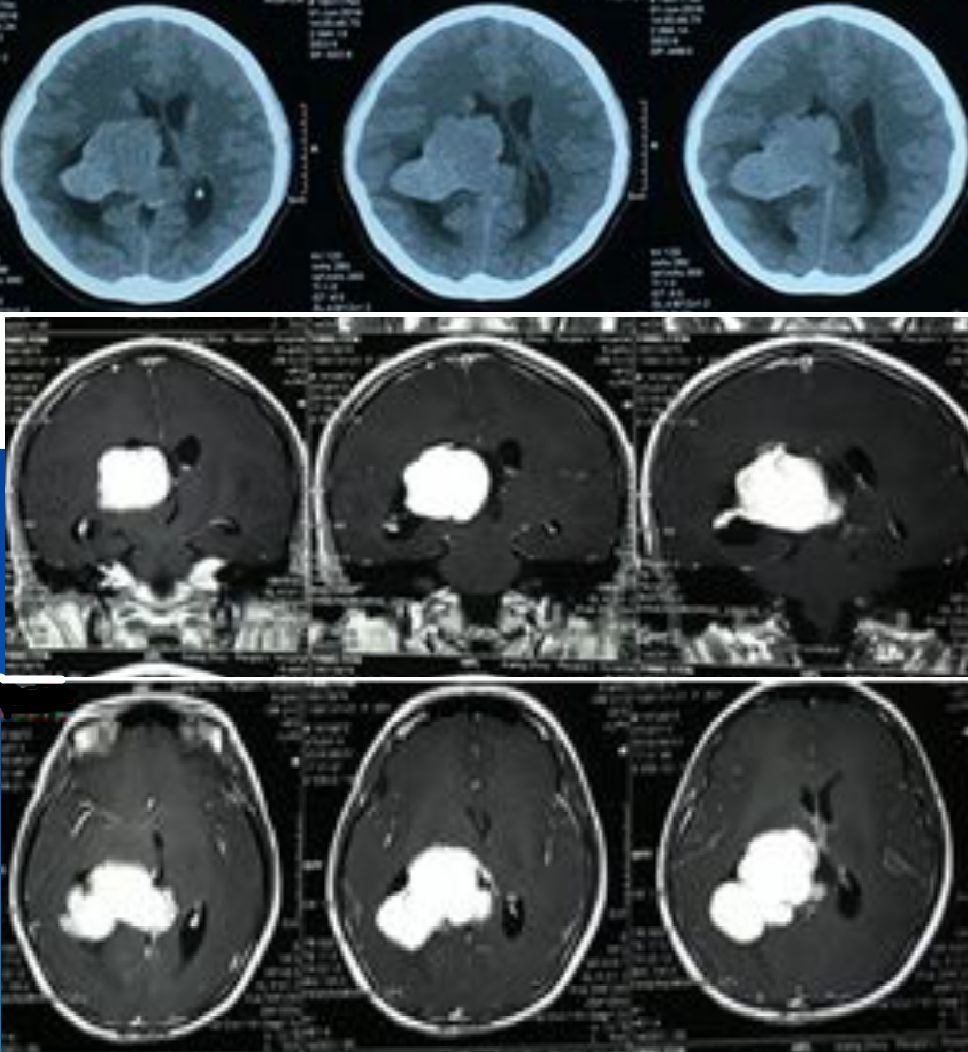

既往病史:2月余前因右侧侧脑室肿瘤,见(图1)行右侧顶枕三角区入路肿瘤切除术,术中见肿瘤呈灰白色、质地韧、血供一般,显微镜下全切除肿瘤,术后病检结果为脑膜瘤、WHOI级。

图1. 磁共振显示右侧侧脑室肿瘤,肿瘤大小约5.0 cm×6.5 cm,呈强化明显。

患者第一次肿瘤切除术后第1天复查头部CT无脑积水,于术后第4天拔出脑室外引流管,术后第14天复查头部MRI无异常(图2),后出院。术后第48天患者常规复查头部MRI(图3)提示右侧侧脑室颞角、后角扩张并周围脑组织水肿、中线轻度移位,由于患者无明显颅高压症状,予以观察并定期复查。患者于术后第62天开始出现头痛,恶心,在当地医院行甘露醇脱水治疗,治疗后症状稍改善,但停用脱水药物时患者头痛恶心呕吐症状就再出现。

图2. 术后第14天复查头部MRI无异常。

图3. 术后第48天患者常规复查头部MRI,提示右侧侧脑室颞角、后角扩张并周围脑组织水肿、中线轻度移位。